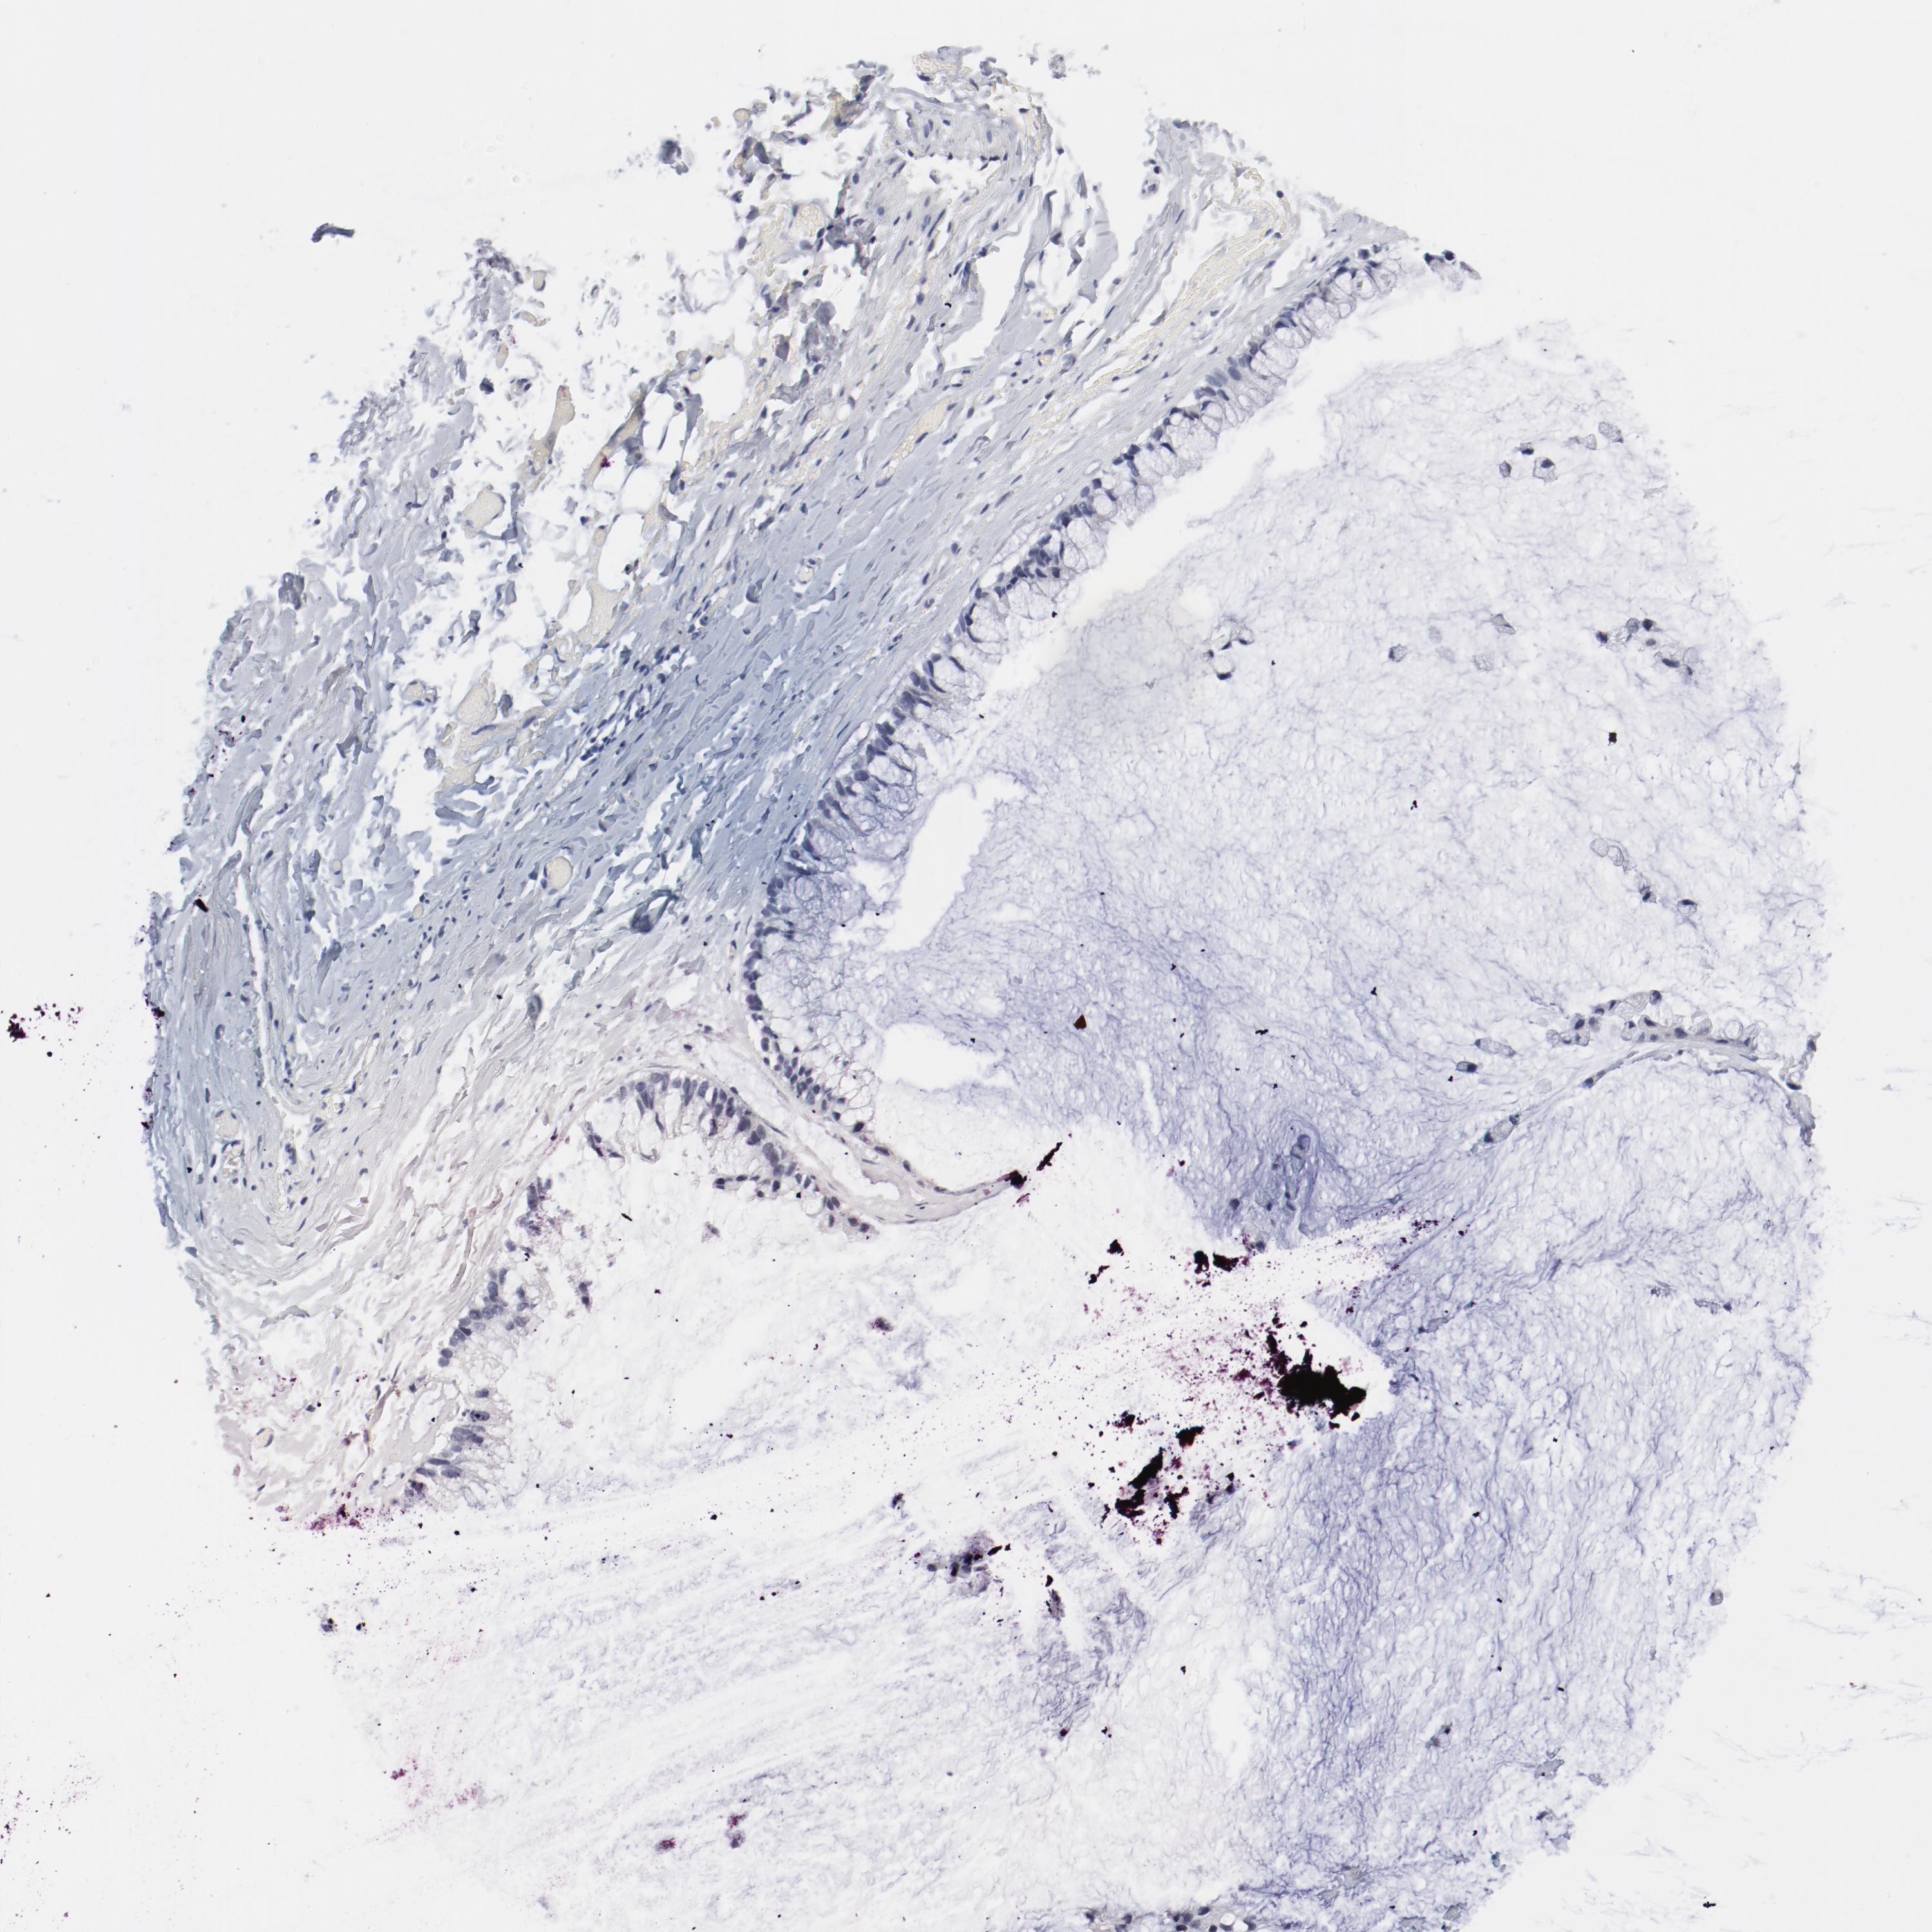

OVARIAN CANCER - Protein expressioni

A mouse-over function shows sample information and annotation data. Click on an image to view it in a full screen mode. Samples can be filtered based on level of antibody staining by selecting one or several of the following categories: high, medium, low and not detected. The assay and annotation is described here.

Note that samples used for immunohistochemistry by the Human Protein Atlas do not correspond to samples in the TCGA dataset.

Antibody stainingi

Antibody staining in the annotated cell types in the current human tissue is reported as not detected, low, medium, or high, based on conventional immunohistochemistry profiling in selected tissues. This score is based on the combination of the staining intensity and fraction of stained cells.

Each image is clickable and will lead to virtual microscopy that enables deeper exploration of all samples and also displays staining intensity scores, fraction scores and subcellular localization as well as patient and tissue information for each sample.

Antibody HPA003514

Staining

High

Medium

Low

Not detected

Intensity

Strong

Moderate

Weak

Negative

Quantity

>75%

75%-25%

<25%

None

Location

Nuclear

Cytoplasmic/membranous

Cytoplasmic/membranous,nuclear

Cystadenocarcinoma, serous, NOS

Cystadenocarcinoma, mucinous, NOS

Carcinoma, endometroid